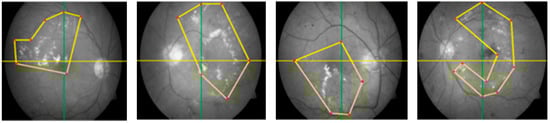

Segmentation is a procedure that helps to eliminate the extra object, refines the texture of the lesion, and recommends a precise position. ROI extraction has many automated and semi-automated methods. We know that automated ROI extraction is usually based on the idea of image segmentation, but there is no single method for ideal segmentation. On the other hand, there are semi-automated techniques based on expert opinion, but human-based extraction has some limitations. To solve this problem, CARGS is employed on DR images, which helps to examine the qualitative nature of data and useful information. This idea uses a group of neighboring seeds for the formulation of an identifiable region, which is entirely different approach than using contagious and connected sets of seeds fixed dimensions of 2 × 2, 3 × 3, 4 × 4, 5 × 5, or 8 × 8. These seeds are in the shapes of irregular polygons with variable radii from the center of their image. This methodology of seed selection ensures the maximum chance of grouping seeds that belong to same region, as shown in Figure 3.

The new scheme avoids domain-specific problems, as fixed dimensions can be useless/not fit for all images, especially images with micro textures like bio medical images, where abnormalities are not observed in some regular shapes but can be seen when drawing irregular polygons with different dimensions. Thus, we can expect calculations to be more accurate because they cover the maximum amounts of interested/abnormal regions (in case of medical images) accordingly. The main advantage of this scheme over a scheme with regular polygons is the segmentation of a fewer possible and more specific homogeneous number of seeds with minimum noise, as shown in Figure 4.

Figure 3. Irregular polygonal seed selection proposed novel mechanism.